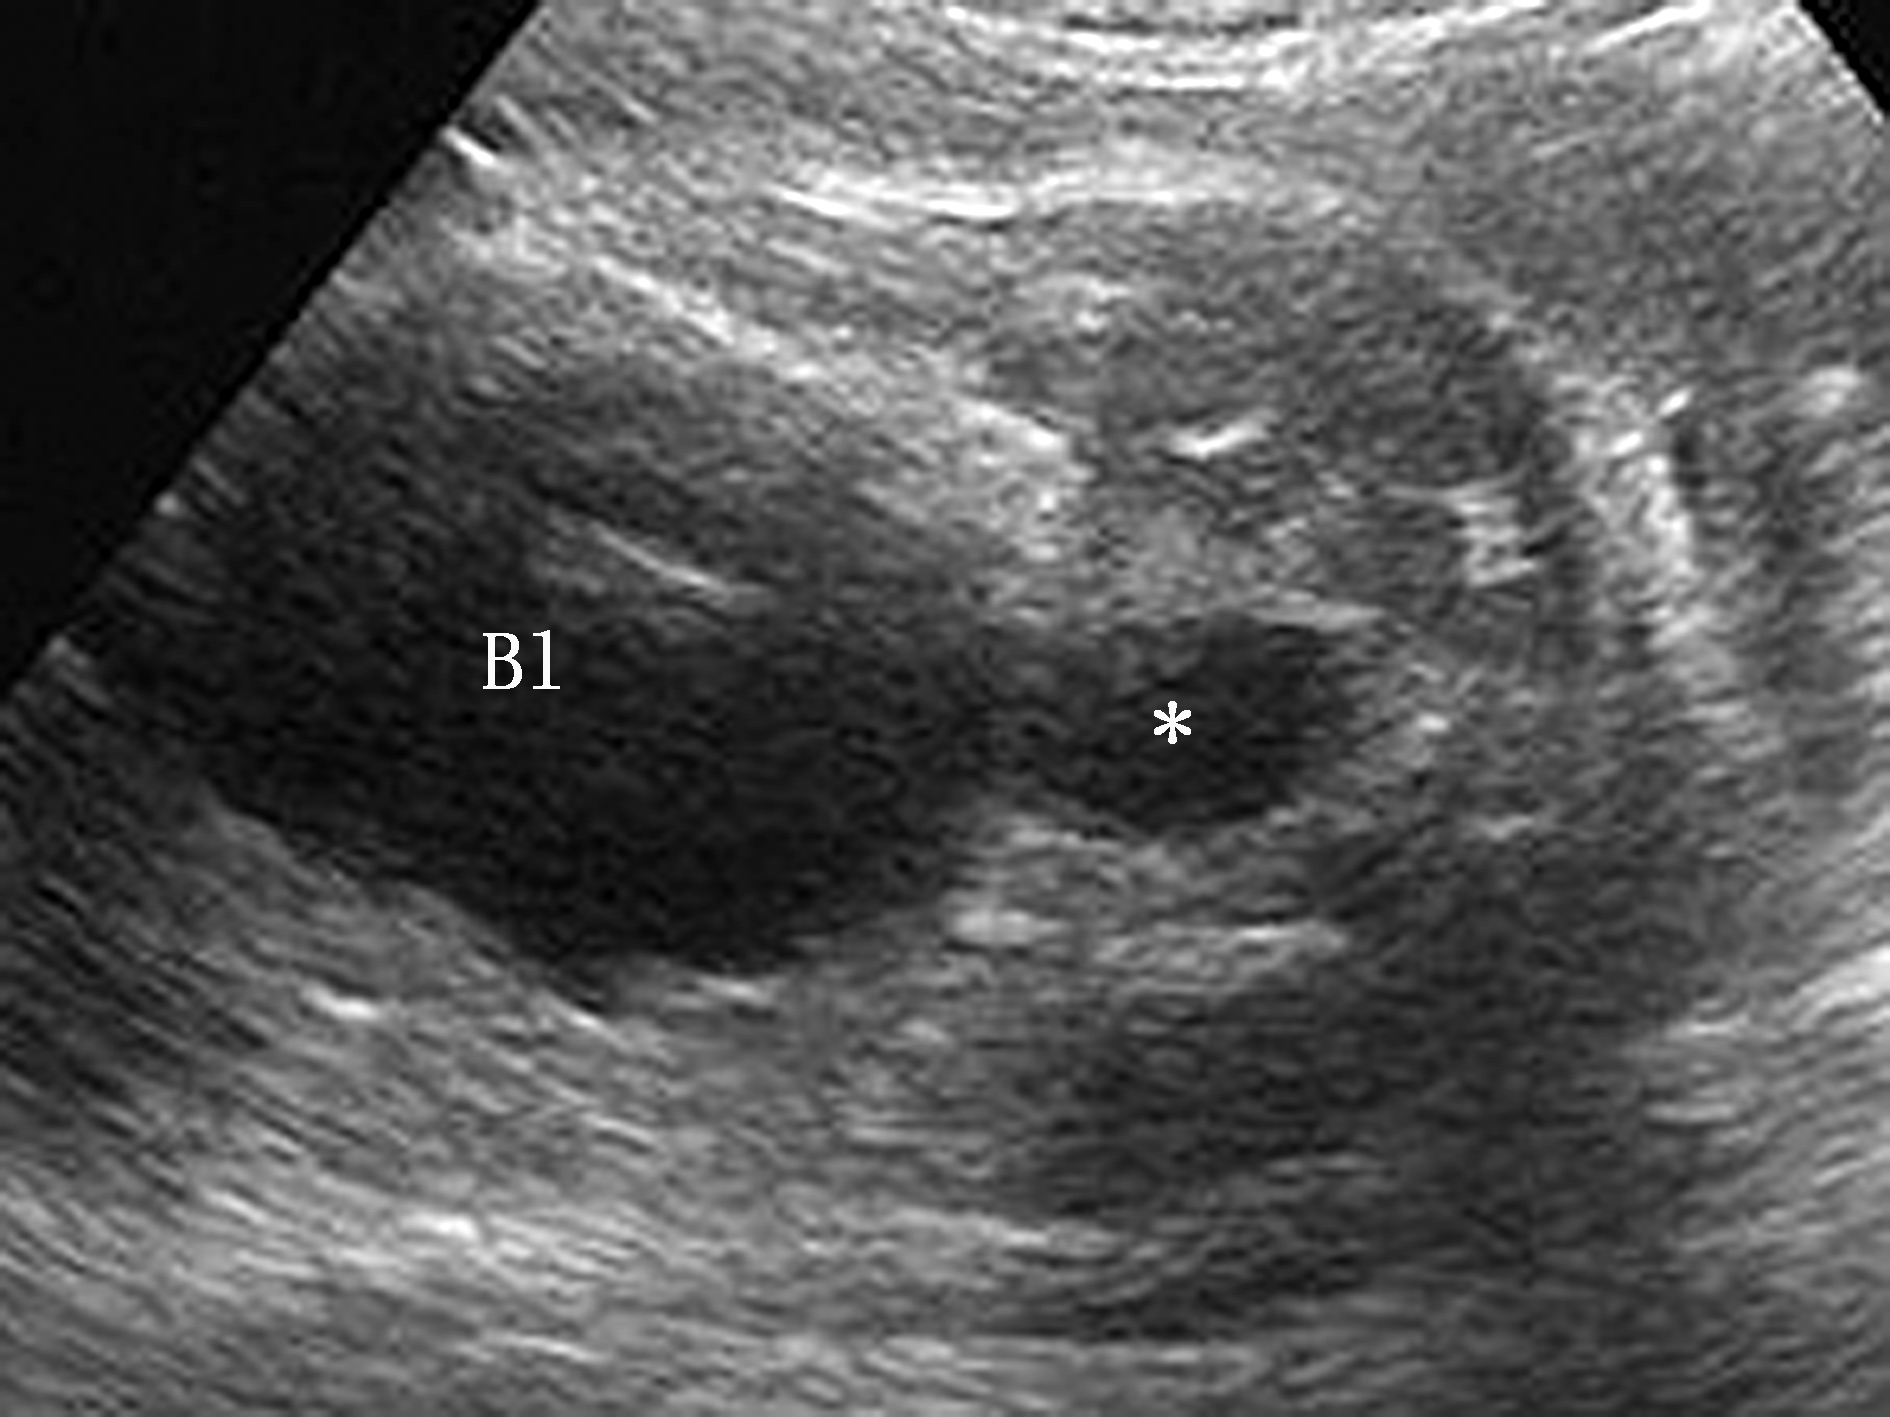

图1 30周胎儿后尿道瓣膜致后尿道扩张声像图,膀胱(Bl)增大,后尿道扩张(*)

超声表现双肾及输尿管扩张,膀胱增大、扩张,膀胱壁增厚、其内缘不规则,50%以上病例发生羊水过少,肾实质回声增强且APD>10 mm或囊性改变表明肾发育不良,若超声检出肾内囊性病变,肾脏发育不良预告值为100%,双侧肾囊性疾病史结果也是致命的。膀胱明显扩张及膀胱壁明显增厚,这是最常见的超声征象,后尿道明显扩张似“钥匙孔”样与膀胱相通(图1),此征象常因平面显示不满意不能显示,肾积水偶可表现为非对称性,可能与尿液流入反流严重的一侧输尿管而进入该侧肾脏有关。当梗阻严重造成膀胱破裂和肾盏破裂时,可形成尿性腹水、腹腔内钙化灶和肾周尿性囊肿。本病只发生在男性,检出性别有助于诊断。